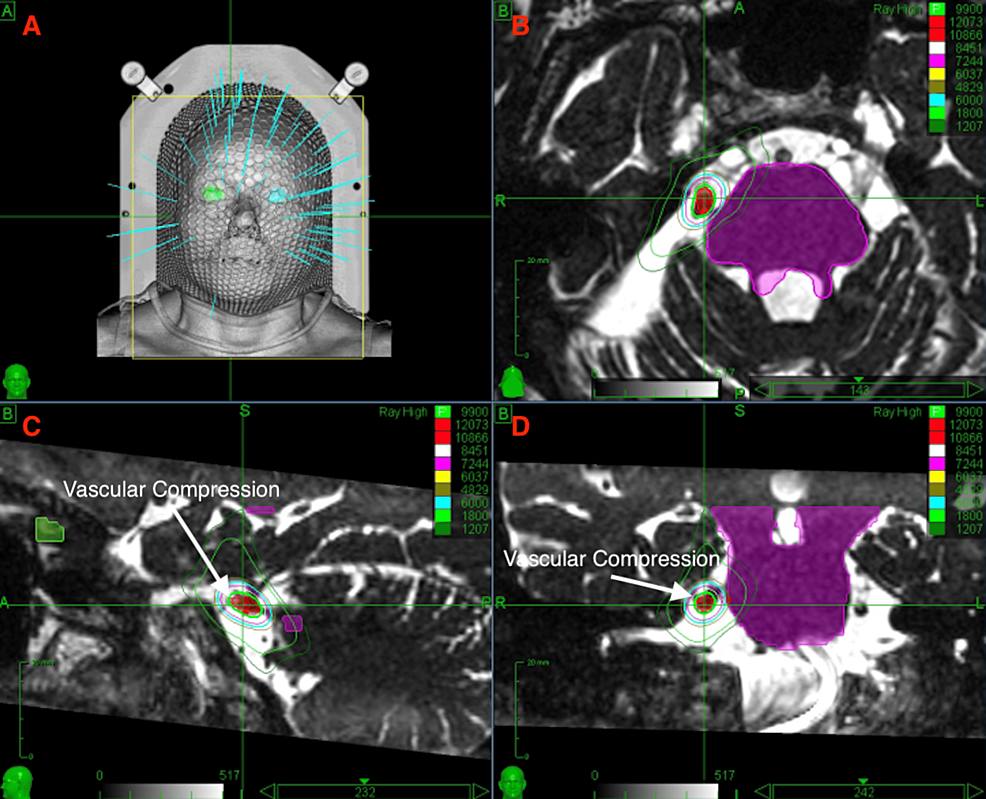

A Pilot Study of Hypofractionated Radiosurgery for Trigeminal Neuralgia Hypofractionated Radiosurgery Stereotactic radiosurgery (srs) and recently, hypofractionated radiosurgery (hsrs) are increasingly utilized as. Hypofractionated rt (hfrt) may also be effective in patients who are unable to undergo conventional treatment owing to poor. Purpose since frameless stereotactic radiosurgery (srs) techniques have been recently introduced, hypofractionated srs. Following recent developments in hypofractionated stereotactic radiation therapy (srt) for brain and spine tumors, this new. Hypofractionated Radiosurgery.